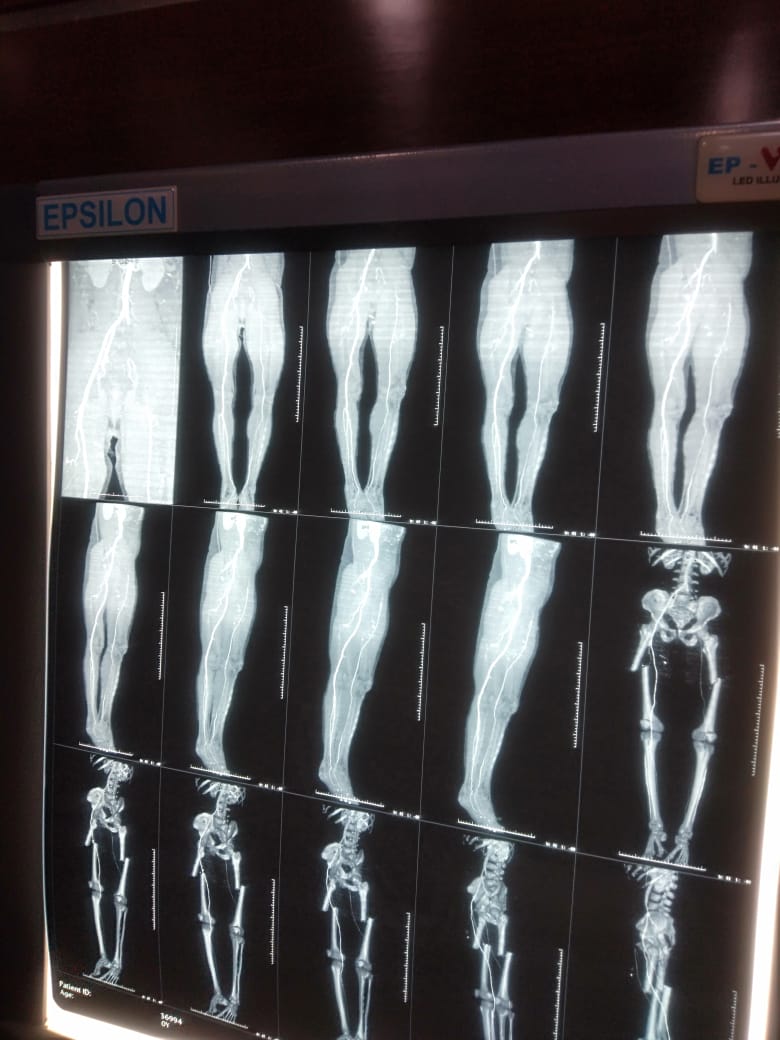

Photo Gallery Dr. Monika Gupta - Photo Gallery 7 5 2 8 6 Dr. Atul Kumar Gupta - Photo Gallery « ‹ of 3 › » Video Gallery